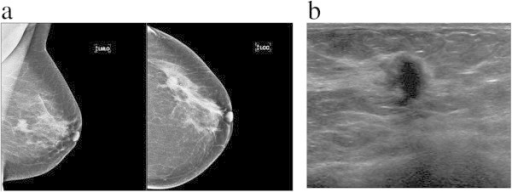

Lump or thickening

Lumps or thickened tissue can occur anywhere in the breast, including up to the collarbone and in the axilla. Breast lumps can present differently in different patients, e.g. they may be hard, soft, painless, painful, fixated, mobile, near the skin’s surface or deep in the breast tissue. A lump can also present as a thickened area of breast tissue that feels different from the rest of the breast.

Invasive ductolobular carcinoma of the breast: spectrum of mammographic, ultrasound and magnetic resonance imaging findings correlated with proportion of the lobular component by G. L. Menezes, M. A. van den Bosch, E. L. Postma, M. A. El Sharouni, H. M. Verkooijen, P. J. van Diest and R. M. Pijnappel is licensed under CC BY 2.0